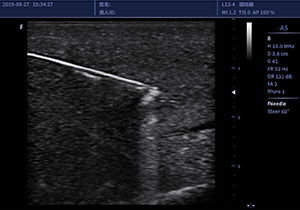

穿刺增强fNERDLE

• 手术室麻醉科/疼痛医学/介入超声医学

丰富的探头群、全面的穿刺套件以及简易的操作流,为手术室、疼痛医学、介入超声提供全面的临床诊疗方案,使超声医学为临床精准治疗保驾护航。